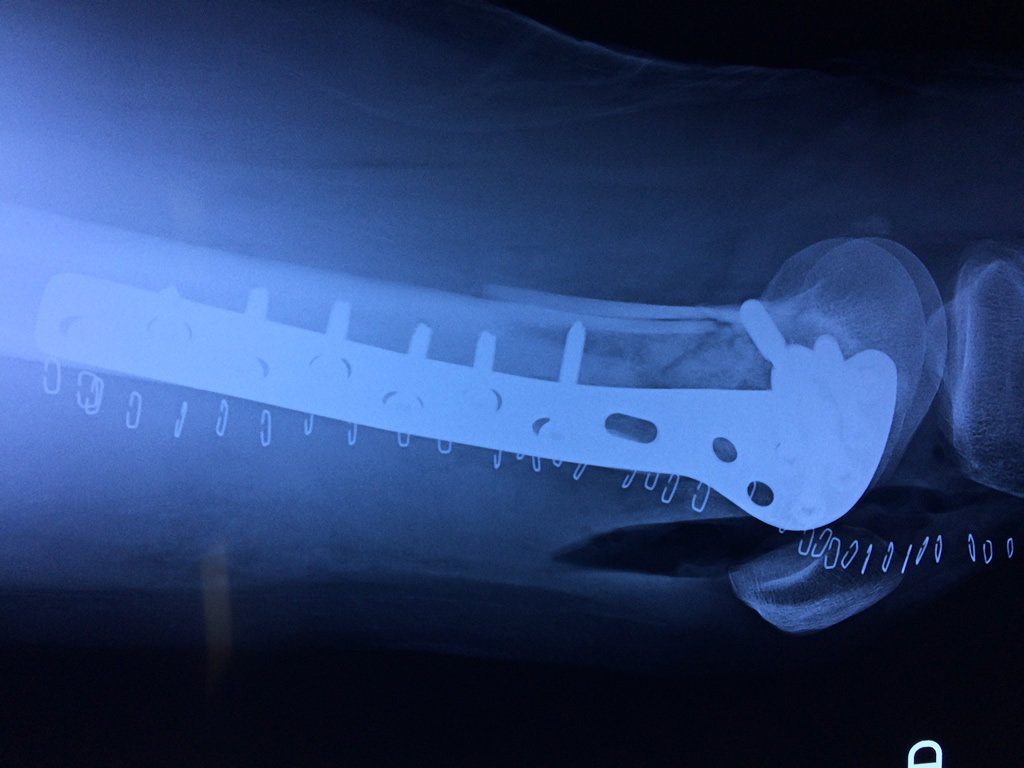

El fémur es el hueso del muslo, el segundo segmento del miembro inferior. Es el hueso más largo, fuerte y voluminoso del cuerpo humano.